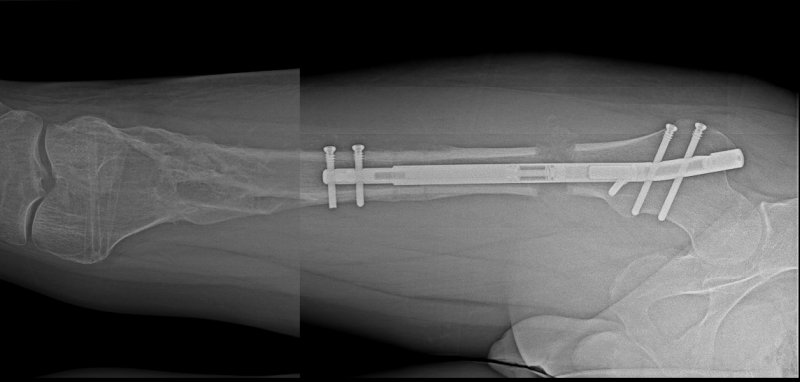

W zeszłym miesiącu taką innowacyjną operację w szpitalu Rehasport przeprowadził dr n. med. Bartosz Musielak, wykonując zabieg wydłużania kończyny dolnej z osteotomią dystrakcyjną i implantacją gwoździa magnetycznego PRECICE. Zabieg wydłużania kończyny dolnej polegał na umieszczeniu wewnątrz kanału szpikowego kości gwoździa magnetycznego rosnącego NuVasive PRECICE z minimalnie inwazyjnym, przezskórnym przecięciem kości. Ten wyjątkowy teleskopowy pręt wyposażony jest w specjalny mechanizm aktywowany przy pomocy zewnętrznego sterownika odpowiedzialnego za stopniowe jego wydłużanie.